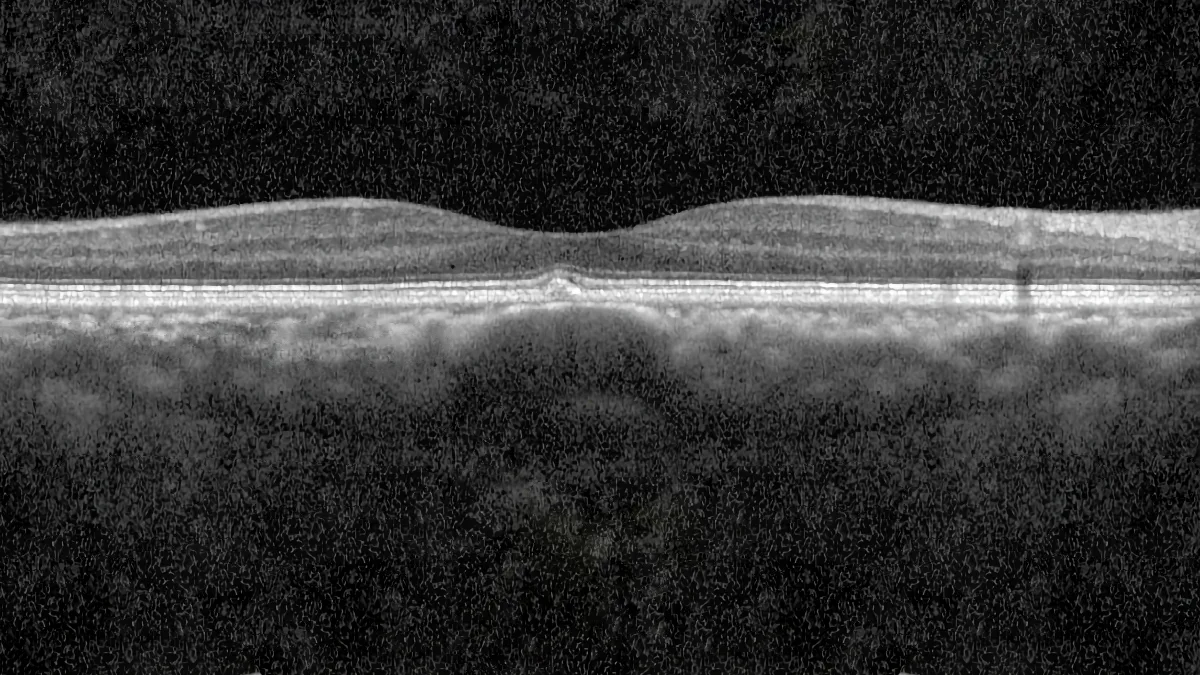

- L'OCT (tomographie en cohérence optique) : c'est l'examen fondamental. En mode EDI (enhanced depth imaging) ou avec la technologie Swept Source, il permet de visualiser en détail les différentes couches de la choroïde, de mesurer son épaisseur et de repérer les pachyvaisseaux et la compression de la choriocapillaire.

Le terme « pachychoroide » vient du grec pachy, qui signifie « épais ». Il désignait initialement un épaississement anormal de la choroïde. Aujourd'hui, la définition est plus précise : la pachychoroide se caractérise par la présence de veines choroïdiennes dilatées (appelées « pachyvaisseaux ») dans la couche de Haller, associées à une compression de la choriocapillaire et à un dysfonctionnement de l'épithélium pigmentaire rétinien, la barrière protectrice entre la choroïde et la rétine.

- L'excavation focale choroïdienne : un amincissement localisé de la choroïde, visible à l'OCT, habituellement sans conséquence sur la vision sauf s'il touche la zone centrale.